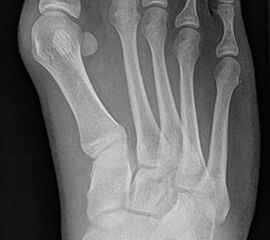

Bei einem juvenilen Hallux valgus handelt es sich um eine schon im Kindes – oder Adoleszentenalter 1 bestehende Valgusdeviation der großen Zehe bei Spreizfuß mit vergrößertem Intermetatarsalwinkel I / II aufgrund einer Adductionsstelllung des Metatarsale I – Metatarsaus primus varus.

Im Gegensatz zum Hallux valgus des Erwachsenen ist die Valgusabweichung der großen Zehe meist geringer ausgeprägt als bei Erwachsenen, der Intermetatarsalwinkel oft stark vergrößert. Die Angaben ab wann der Intermetatarsalwinkel als vergrößert gilt schwanken zwischen > 9° 2 und >14°3. Das Ausmaß der Beschwerden korrelieren nicht mit dem Auftreten und dem Schweregrad der Deformität (Zollinger 1990, Zollinger 1993). Begünstigend wirkt eine Schrägstellung des ersten Tarsometatasalgelenkes (Hefti 1998) und eine Hypermobilität dieses Gelenkes 2 in Kombination mit einer Bindegewebsschwäche. Häufig liegt eine positive Familienanamnese vor. In einer Untersuchung von Coughlin fand sich eine Vererbung über die mütterliche Linie in 72%, ein milder bis stark ausgeprägter Knick-Senkfuß in 17% (das entspricht der Quote von Knick-Senkfüßen in der Normalbevöl­kerung) aber in 22% ein Pes adductus, das ist wesentlich mehr als in der Normalbevölkerung zu erwarten wäre 4. Auch für Hefti (1998) gilt der Pes adductus als Komponente des Sichelfußes als begünstigend. Zur Inzidenz des Hallux valgus juvenilis finden sich je nach Autor verschiedene Angaben. Nach Auswertung von Schuluntersuchungen liegt die Häufigkeit zwischen 1,6 % bis 17% 56. Häufig tritt die Fehlstellung doppelseitig auf. Der Anteil der betroffenen Mädchen liegt 4-5x höher als bei Jungen (Lamprecht 2015).

Auch einige Syndrome gehen mit der Ausbildung eines ausgeprägten Spreißfuß mit Hallux valgus einher. Auf der Abbildung ein junger Erwachsener mit Trisomie 21.

• Hallux valgus Winkel

• Intermetatarsalwinkel I zu II

• Distaler Metatarsale Gelenkwinkel (PASA)

• Pes metatarsus adductus